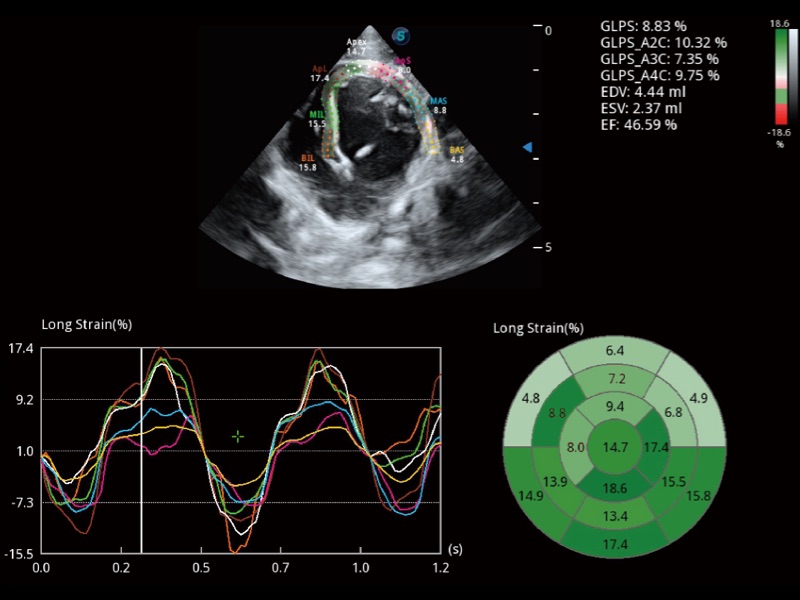

能够基于左心室壁追踪和辛普森法,自动计算射血分数,支持多个可移动点描迹,与手动测量相比,极大节省了动物医生的时间和精力。

具备多种协议可选,同时支持17阶段划分法和专业的SE报告。